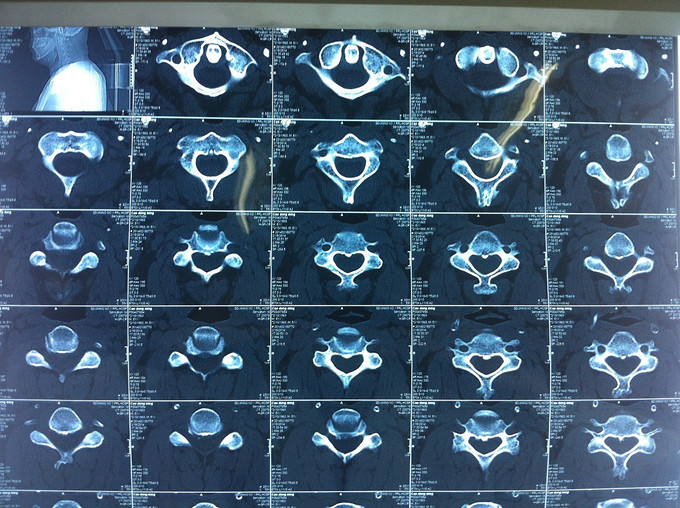

查体:颈后部压痛,颈部活动受限,双侧前臂及手感觉减退,双侧伸腕、伸肘肌肌力4级,双侧霍夫曼综合征阴性,双下肢感觉无减退,双下肢肌张力高,巴氏征可疑阳性,辅助检查: X-ray:劲椎退行性变 CT:颈椎间盘突出,腰5/6 MR:颈椎间盘突出,颈5/6节段明显